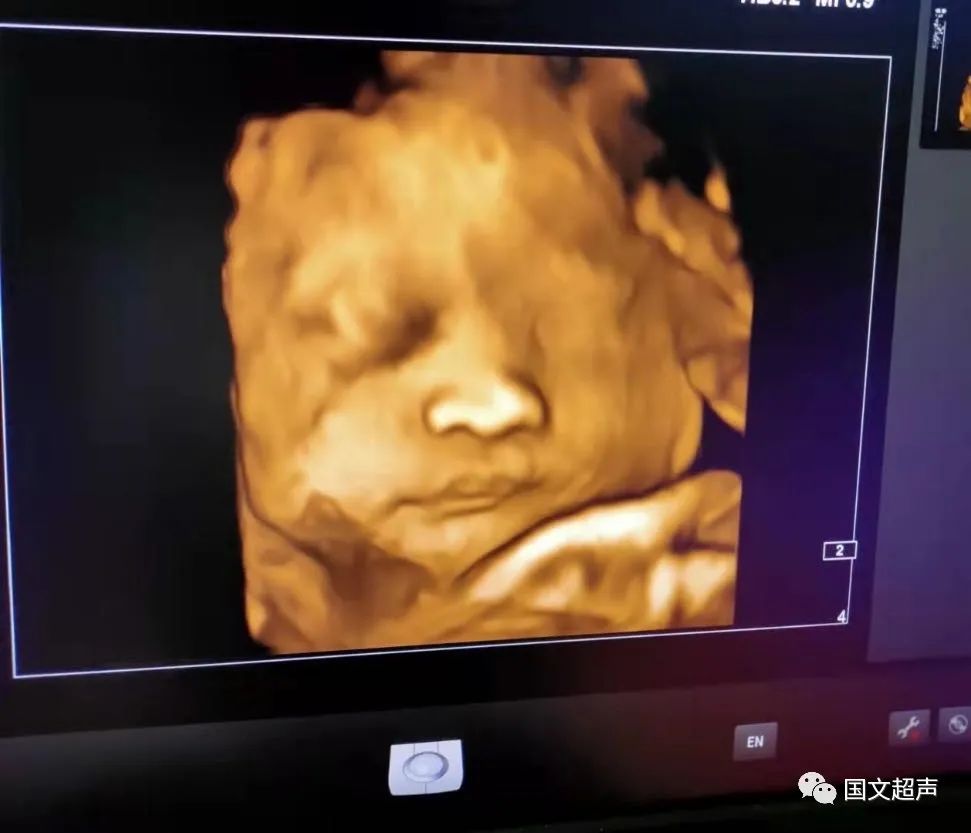

2.孕22周~26周,這個時期檢查,胎兒大小及羊水適中,胎兒活動度大,有利于觀察宮內(nèi)胎兒的生長發(fā)育情況,如果胎兒位置不好,也可以通過孕媽的走動改變胎兒體位,觀察到所需的留圖切面和四維圖像。